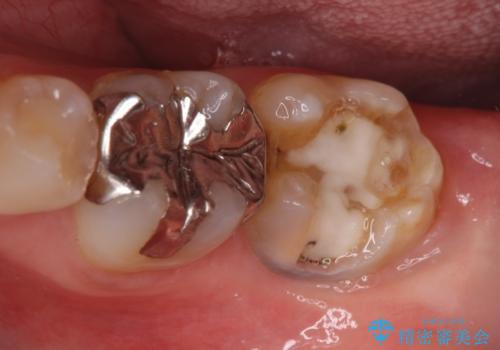

- 奥歯の虫歯と前歯のデコボコや突出感を気にして来院された患者様です。

矯正治療後は、奥歯の虫歯や銀歯を補綴・修復治療することとしました。